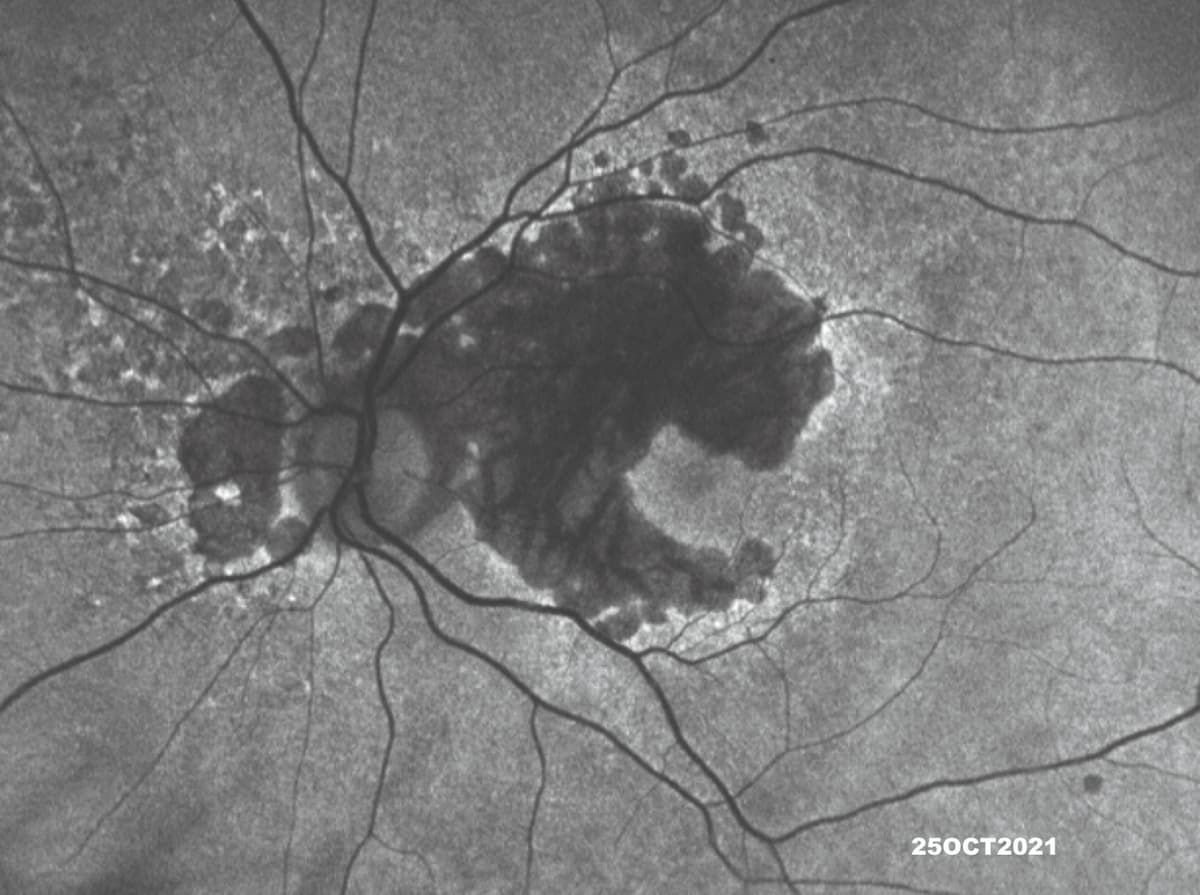

Fundus autofluorescence (FAF) allows visualization of the typical hallmark hyperautofluorescence pattern along the border of a GA lesion. The technique uses the natural fluorescence of lipofuscin in the retinal pigment epithelium (RPE) and can also help in differentiating IRDs, particularly by identifying RPE changes and atrophy (Figure 1).

Figure 1 (top): A blue fundus autofluorescence image of the left eye of a woman aged 86 years with a multifocal pattern of geographic atrophy with perilesional hyperautofluorescence.